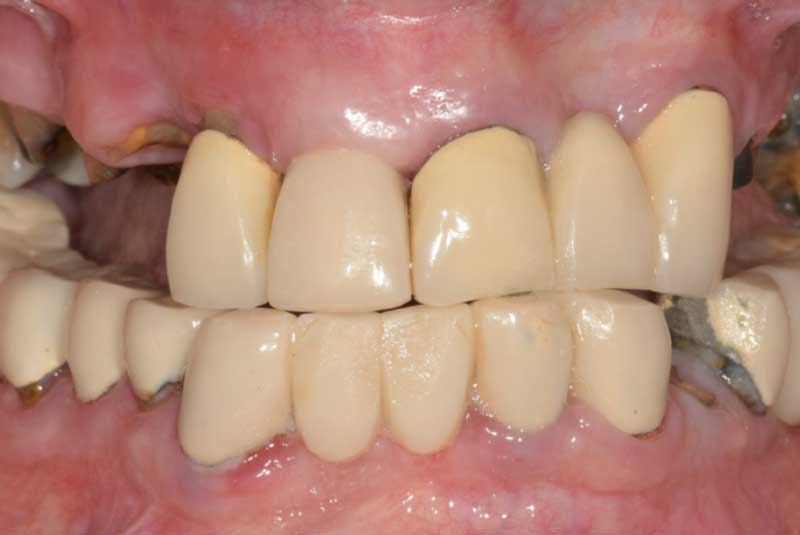

The patient had her implants placed 20 years ago. Four implants, particularly in the maxilla, were not positioned ideally for me to utilize and restore, while the four implants in the mandible were outdated and no longer functional. The patient's primary concern is to restore both function and aesthetics.

All on 6: Facial cut back (PFZ) Zirconia Full arch prosthesis for Maxilla and Mandible Before & After